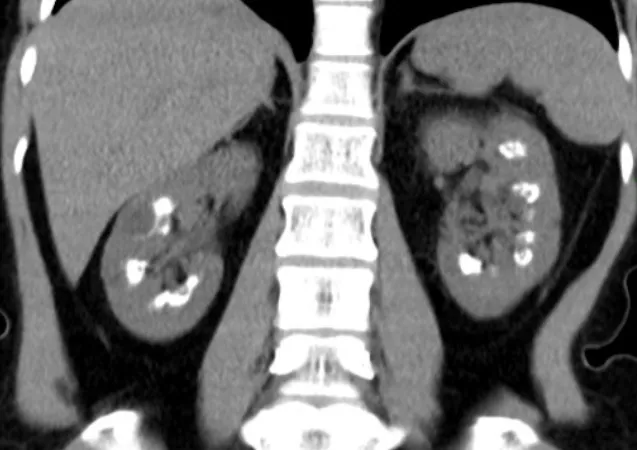

O paciente está congesto? O que realmente ajuda na prática?